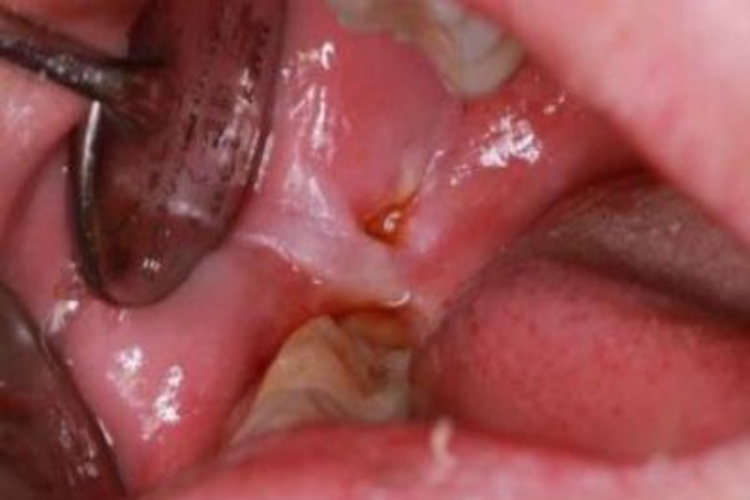

创伤性溃疡的损害可发生在口腔,临床上可表现为口腔内侧出现溃疡,溃疡面糜烂、发白,有出血,创面面积较大,口腔动作牵扯颊部时疼痛明显。

患者牙齿咀嚼食物时误伤口腔黏膜,可导致口腔内侧出现创口,在口腔环境及食物残渣刺激下,创口处可发生溃烂,即出现糜烂、发白的溃疡。

患者首先应去除局部刺激因素,如拔除残根,修改或拆除不合适的修复体,磨改锐利的牙尖或切缘,以免发生二次损伤。同时,若患者伴随着剧烈疼痛,可在医生指导下使用消炎镇痛药,以防止感染和镇痛,如复方氯己定含漱液、复方角菜酸酯乳膏等。